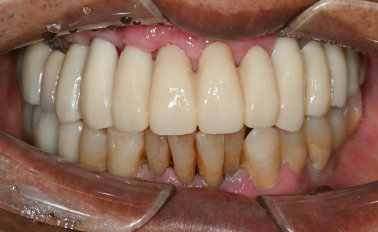

반갑습니다, 하루임플치과입니다. “앞니가 다 썩었어요.” “이가 빠진 지 오래됐고, 남아 있는 앞니도 흔들려요.” 이렇게 말씀하시며 내원하시는 분들이 종종 계십니다. ...

치과에 오시는 많은 분들이 “이 치아는 빼야 하나요?” “임플란트를 해야 한다고 하던데 맞나요?” 라는 고민을 가지고 계십니다. 특히 앞니처럼 심미성·...